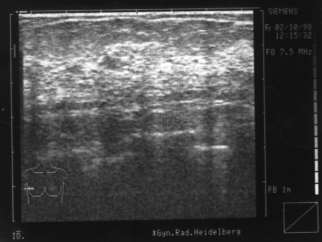

Innerhalb von 2 Tagen wächst dieser große Knoten in der linken Brust der Klientin. Der Prof. will die Brust abnehmen. Die Klientin aber nutzt die kurze Zeit bis zum OP-Termin zur Selbstheilung und läßt sich von Brigitte mit 6 Synergetik Therapie Sitzungen helfen, den Hintergrund selbst aufzulösen. Dazu mußte es einen konkreten Auslöser mit dem Thema „Kind“ geben, der so schnell arbeitete und den Knoten produzierte. Dieser war leicht zu finden und der wirkende Kontext in der Innenwelt wurde verändert. Der Prof. staunte nicht schlecht, als er den Knoten per Ultraschallbild nicht mehr finden konnte. ... Er interessierte sich für die Synergetik Therapie und lädt Brigitte Schiechel zur Zusammenarbeit ein.

Vorher:

Nachher: